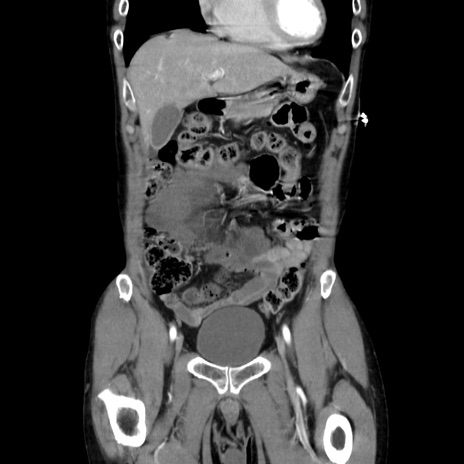

症例37(冠状断像)

【症例】40歳代 男性

【主訴】腹痛

【現病歴】4時間ほど前に電車に乗車中に臍部上より腹痛出現。徐々に増悪し起立困難となり、救急外来受診。生ものは数日食べていない。今朝お雑煮を食べた。

【身体所見】BT 36.8℃、BP 117/84mmHg、HR 91/min、SpO2 97%、苦悶様、腹部:臍上部広範囲圧痛あり、反跳痛±

【データ】WBC 8100、CRP 0.03